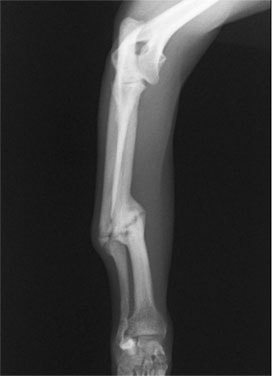

ペルシャ猫 11ヶ月齢 雄

他院にて左大腿骨遠位の成長板骨折(salter-harrisⅠ型)が認められており、治療相談を目的として来院。当院にて、キルシュナーワイヤーを用いたピンニングにより骨折部位の整復を行いました。術後の経過は良好で、現在も経過観察中です。

術前レントゲン